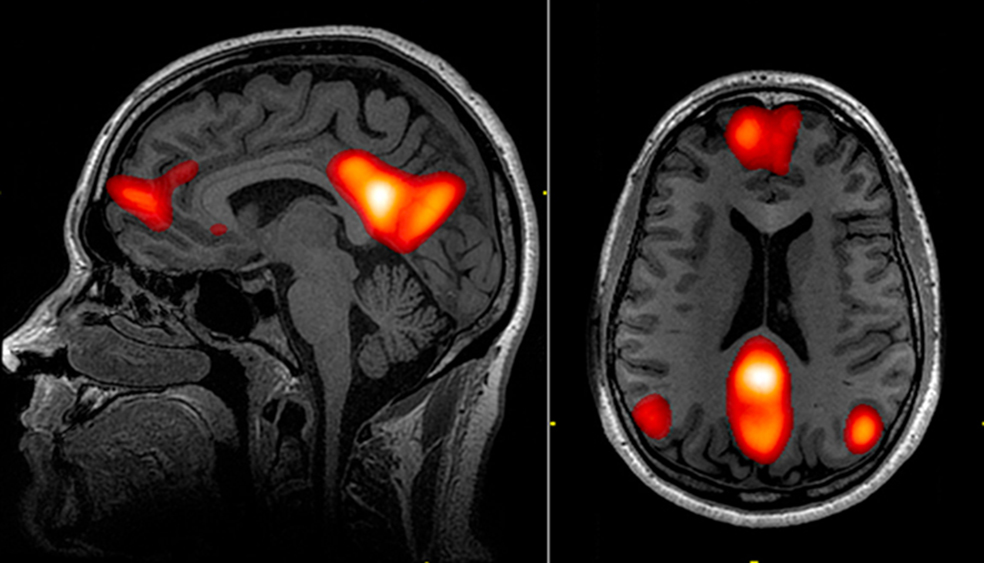

La responsable de este 'efecto ducha', en términos fisiológicos, es la red neuronal por defecto, una función de nuestro cerebro que se activa cuando entramos en modo 'desconexión'. Las resonancias magnéticas funcionales han permitido en los últimos años visualizar cómo la actividad de esta red se desarrolla en los lóbulos temporal, parietal y prefrontal. Cuando desconectamos o dejamos vagar nuestra mente, esa red se activa como una onda que fluctúa cada ciertos milisegundos. El cerebro relajado, por ponerlo en palabras sencillas, no se 'apaga' sino que se mueve en otra 'longitud de onda'.